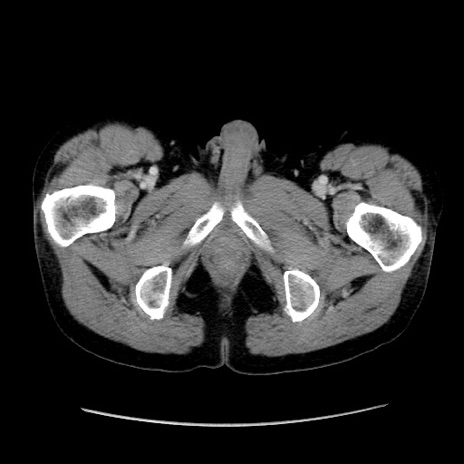

症例37(横断像)

【症例】40歳代 男性

【主訴】腹痛

【現病歴】4時間ほど前に電車に乗車中に臍部上より腹痛出現。徐々に増悪し起立困難となり、救急外来受診。生ものは数日食べていない。今朝お雑煮を食べた。

【身体所見】BT 36.8℃、BP 117/84mmHg、HR 91/min、SpO2 97%、苦悶様、腹部:臍上部広範囲圧痛あり、反跳痛±

【データ】WBC 8100、CRP 0.03